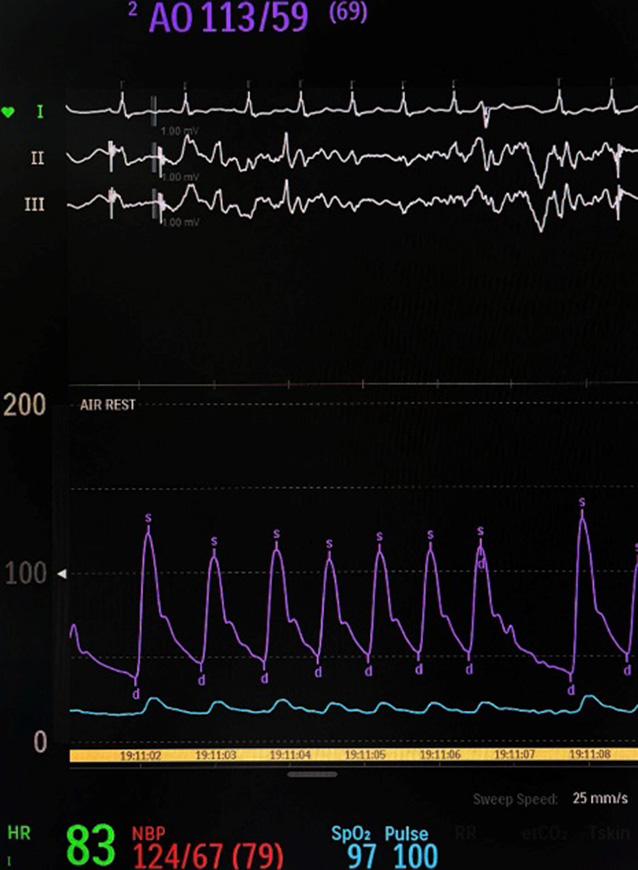

Invasive AP monitoring was performed under fluoroscopic guidance in the extracranial segment of the main artery (C1 segment of the ICA) using a standard aspiration catheter (length – 132 cm; inner diameter – 1.80 mm) and in the MCA distal to the thrombus using a standard microcatheter (length – 153 cm; inner diameter – 0.81 mm) prior to the deployment of a stent retriever. The results were recorded using an HP Engage Flex Pro portable computer (HP Inc., USA) connected to a compatible pressure transducer (part of the Philips Azurion 7 angiographic hemodynamic monitoring system; Philips Medical Systems Nederland B.V., Best, Netherlands). After calibration, the transducer was connected via a fluid-filled line to the catheter cannula. Calibration of the sensor was performed before each measurement (Fig. 2).

A B

Fig. 2. Invasive AP waveform recording: A – distal to the thrombus in the middle cerebral artery (MCA); B – proximal to the thrombus in the internal carotid artery (ICA)